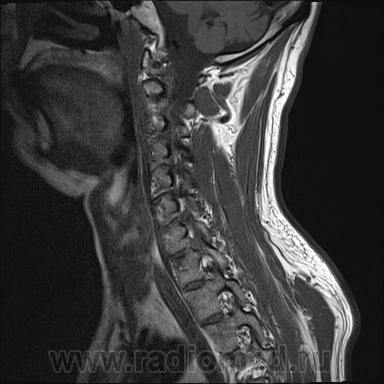

Грыжа диска. А где аксиалы?

Шейный остеохондроз.Грыжа С7-Th1.Не исключено наличие миелопатии на этом уровне, но боюсь ошибиться-изображения мелковаты ,идаже кажется, что есть повышение МРС от спинного мозга по Т1( скорее всего-артефакты?).

Левосторонняя парамедианная с компрессией корешка.

а это не перидурит??? смотрели месяц назад (в начале заболевания) было меньше.

Посмотрите на STIRе. Если жидкости нет, то простая грыжа. На этих сканах вообще-то жидкости не видно. За месяц грыжа могла и подрасти, смотря как лечили.

По-моему, только грыжа.